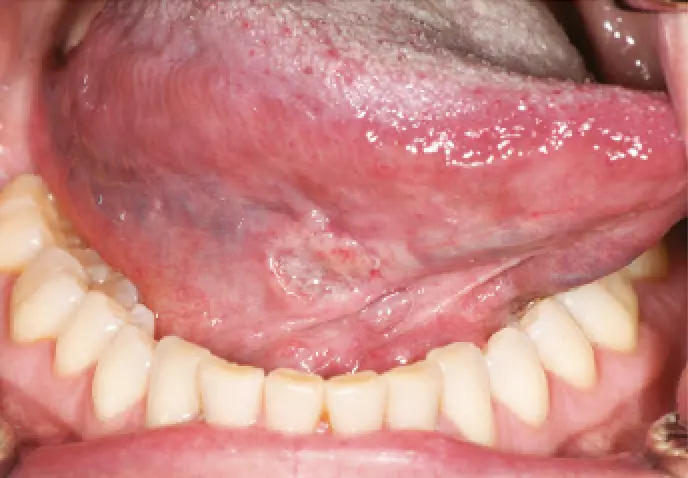

Oral squamous cell carcinoma (SCC) is the most common oral malignancy and typically presents:

- as a non-healing ulcer

- with indurated, rolled edges

- often on the lateral tongue or floor of mouth

Image 1: SCC of the right tongue (source: https://www1.racgp.org.au/ajgp/2020/september/common-benign-and-malignant-oral-mucosal-disease)